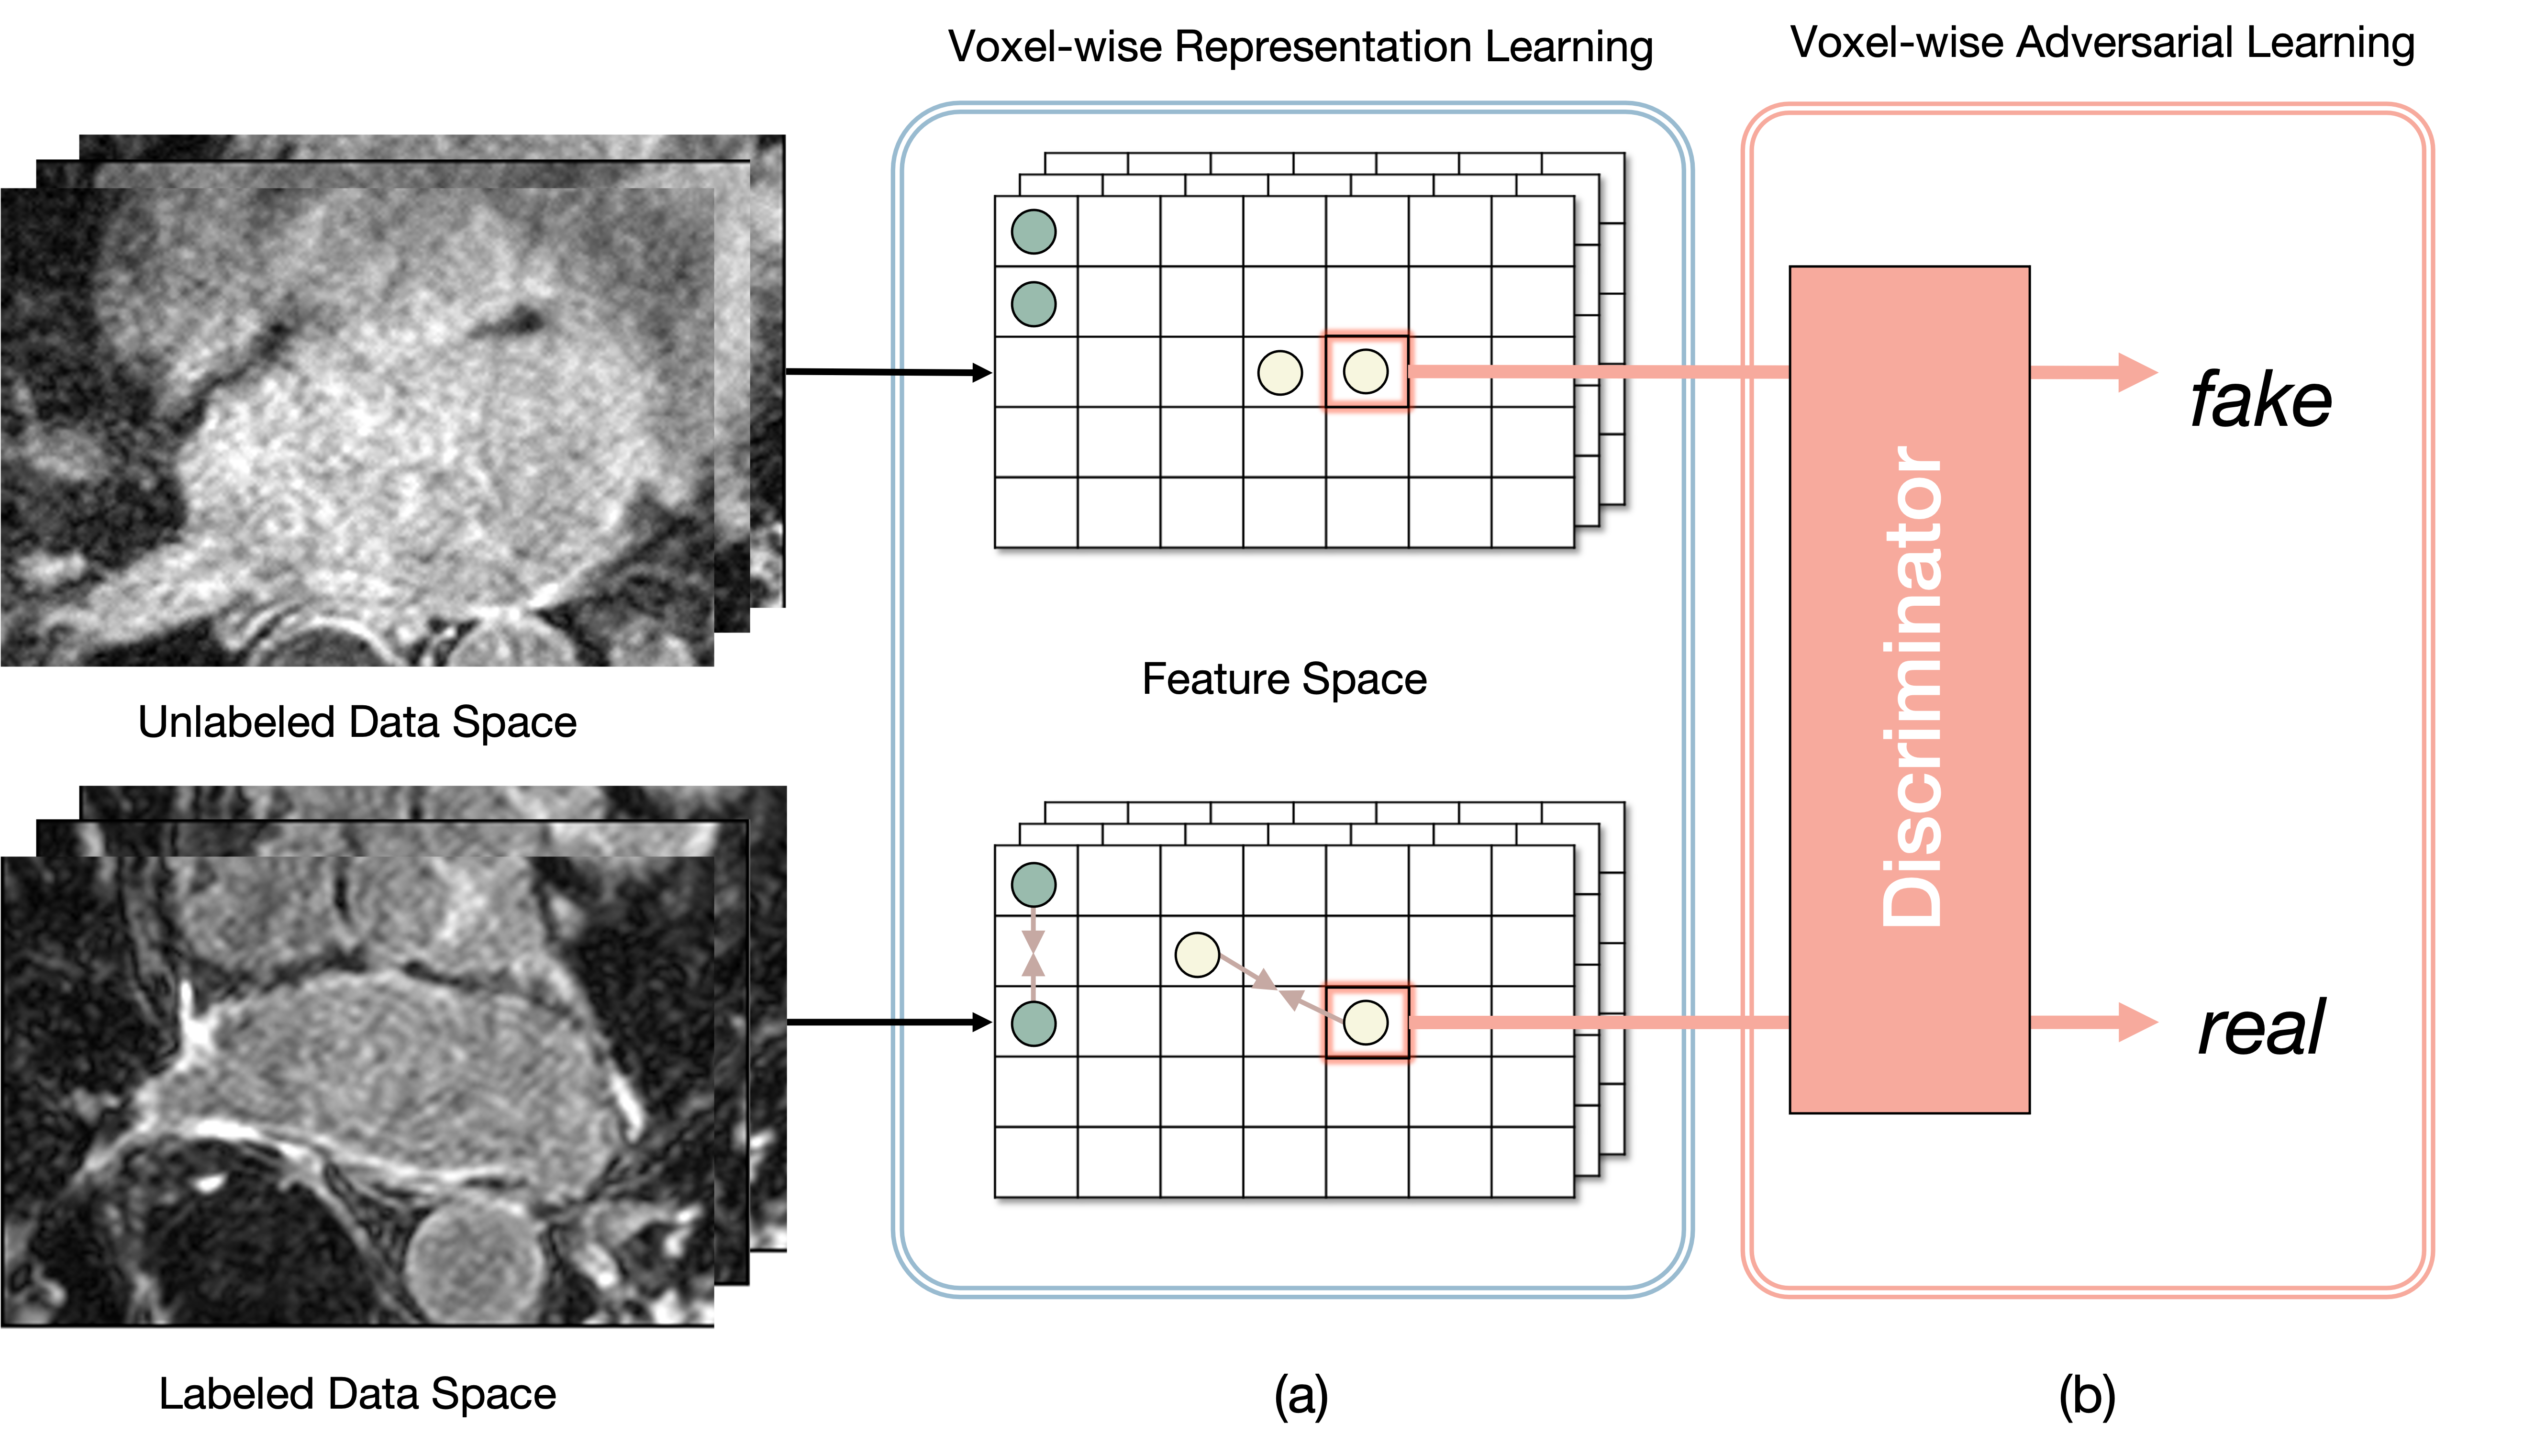

In this paper, we propose a novel adversarial learning-based method to incorporate unlabeled data to improve the network performance. We propose a context-aware semi-supervised segmentation method for efficiently learning the distributions of labeled and unlabeled datasets. To resolve the aforementioned problems of recent studies, we considered voxel-wise features from multiple hidden layers, which include both the local and global information of the data, as an input to our voxel-wise feature discriminator to embed distributions of unlabeled datasets. As illustrated in Fig. 1b, the job of this discriminator is to determine if a voxel-wise feature belongs to labeled data or unlabeled data (real for labeled data and fake for unlabeled data). This voxel-wise feature discriminator assumes the form of a multitask discriminator that can learn distributions from different classes simultaneously, thereby allowing us to embed class-specific context-aware features in the embedding space. Furthermore, we propose an improved voxel-wise representation learning method (Fig. 1a) for labeled data. To effectively embed unlabeled data, we are required to implement well-distributed features from labeled data prior to adversarial learning. In our previous study [14], we presented an explicit representation learning method for a supervised segmentation task by defining voxel-level feature relations. We adjusted this previous method to embed feature representations from labeled data without information loss using a multiresolution context resizing technique. Moreover, we used the Bootstrap Your Own Latent (BYOL) approach [15], instead of SimSiam [16], for learning stability.

We aim to learn feature representation (i.e., local and global features) from both the labeled and unlabeled datasets. To achieve this, we propose a context-aware semi-supervised segmentation method that can be incorporated into a segmentation network (i.e., VNet [30]). The overall architecture of semi-supervised segmentation is illustrated in Fig. 2. There exists a backbone network (i.e., VNet [30]) that takes labeled and unlabeled data (i.e., CT scans) as the inputs. We assume a set of training sets containing labeled data and unlabeled data, where . We denote the labeled set as and unlabeled set as , where represents the 3D volume, and denotes the ground-truth label. The proposed architecture for semi-supervised learning consists of two parts: voxel-wise representation learning (the blue box in Fig. 2) and voxel-wise adversarial learning (the red box in Fig. 2). Features from the hidden layers of the backbone network pass through each part to learn feature representations from and . The voxel-wise adversarial learning method takes voxel-wise features from and , after which it learns class-specific data distributions. The voxel-wise representation learning method uses voxel-wise features from and improves current embeddings by defining feature relations from the same class. In Section III-A and III-B, we describe the details of these methods. In Section III-C, we explain the overall training process of our proposed method.

III-A Voxel-wise Adversarial Learning

To leverage a large amount of unlabeled data, the network must be able to learn feature representations using only CT images. Previous consistency-based methods [10, 11] have applied a consistency loss function and trained the network for consistent prediction with perturbed or transformed outputs. The consistency loss is computed between and for labeled and unlabeled data. However, this loss is computed in the last layer (i.e., decision space), which embeds only the local features of data. Moreover, it penalizes voxel-wise consistency ignoring class-specific information. It is also problem in [13] that embedded shape-aware global features are only limited to a single class.

To resolve this problem, we propose a novel voxel-wise feature discriminator for embedding class-specific features of both labeled and unlabeled data. As presented in Fig. 3a, our voxel-wise feature discriminator takes a set of multiresolution features, , as an input, where denotes an encoder of the backbone, and denotes features from the hidden layer. These features from multiple hidden layers pass through the convolution layer to adjust the channel size, and each feature is upsampled to the same spatial size. Such features from multiple hidden layers are fused into one by adding an operation and a convolution layer. Thereafter, voxel-level features (-d vector) from this fused feature, , pass through a voxel-level feature discriminator, which consists of two multilayer perceptron networks (MLPs) and prediction layer (i.e., linear branch). The number of prediction layers corresponds to the number of class (in case of LA dataset, there exist two classes; foreground and background). The voxel-level features from different classes pass through different prediction layers. To specify the class of each voxel-level feature, we use ground-truth label for labeled data and pseudo-labels for unlabeled data, which can be computed using the following equation:

This different prediction branches enable multiple simultaneous adversarial classification tasks. We define features from labeled data as real and those from unlabeled data as fake so that the encoder of the segmentation network (generator) can generate voxel-level features of unlabeled data with a distribution similar to that of voxel-level features of labeled data. This forces the distributions of class-specific voxel-level features from both labeled and unlabeled features to be close. In this manner, the segmentation network can learn class-specific context-aware features more effectively. The encoder can embed both local and global features using a multiresolution context-fusion technique. In representing the voxel-wise feature discriminator, we can define our proposed adversarial loss function as follows: